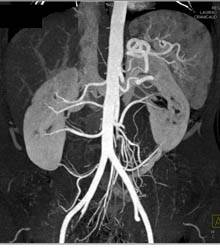

Multiple Renal Arteries